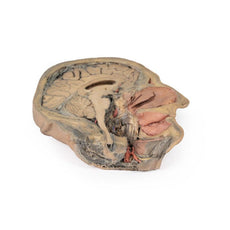

This 3D model presents the superficial anatomy of the face and head, and compliments the superficial facial anatomy

of our HW 44 model with a more expanded dissection across the scalp and occipital regions.

The superficial

neurovascular and muscular structures in the face largely mirror the structures described in reference to our HW 44

specimen (see description), although the terminal branches of the facial nerve (CNVII) can be largely followed

across a longer course from the parotid gland and the platysma muscle has been retained superficial to the mandible

and extends towards the neck.

In contrast to the HW 44 specimen, this model has a more expansive superficial

dissection inferior to the external ear and across the posterior scalp and occipital region. This allows for an

expanded appreciation of the neurovascular distribution of the supraorbital and supratrochlear nerves and arties

with the superficial temporal artery. Inferior to the ear, the retromandibular vein has been exposed with the

ascending fibres of the great auricular nerve on its superficial surface (and further branches of this nerve on the

surface of the sternocleidomastoid muscle). At the posterior border of the sternocleidomastoid muscle the lesser

occipital nerve is just preserved, near the exiting and ascension of the occipital artery and vein near the

trapezius muscle towards the posterior scalp. Surrounding the external ear are fibres of the auricularis superior

and posterior muscles. Near the margin of the dissection window posteriorly the deep fibres of the occiptalis muscle

can be seen integrated into the epicranius (occipitofrontalis) muscle.